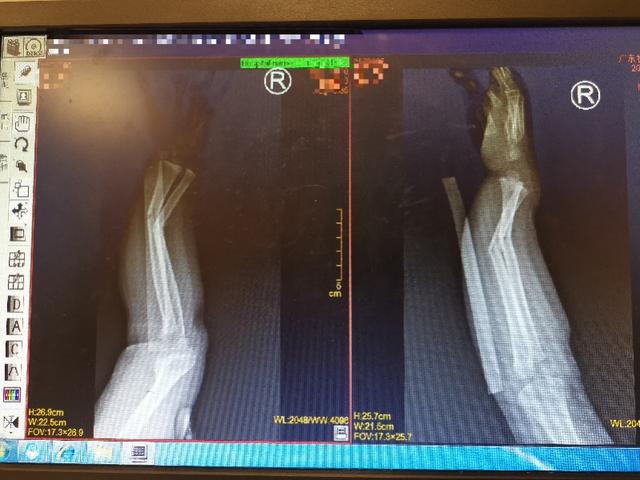

骨科医生李煜首先仔细看了片子,发现小明的右尺骨和桡骨骨折。和家人充分沟通后,他说孩子还小,麻醉和手术风险巨大。同时手术复位容易留下疤痕,对孩子来说是难以承受的痛苦。但是小明的伤情严重,医生的复位技术要求极高。

照片显示骨折。

复位后,x光片显示骨折几乎完全复位。